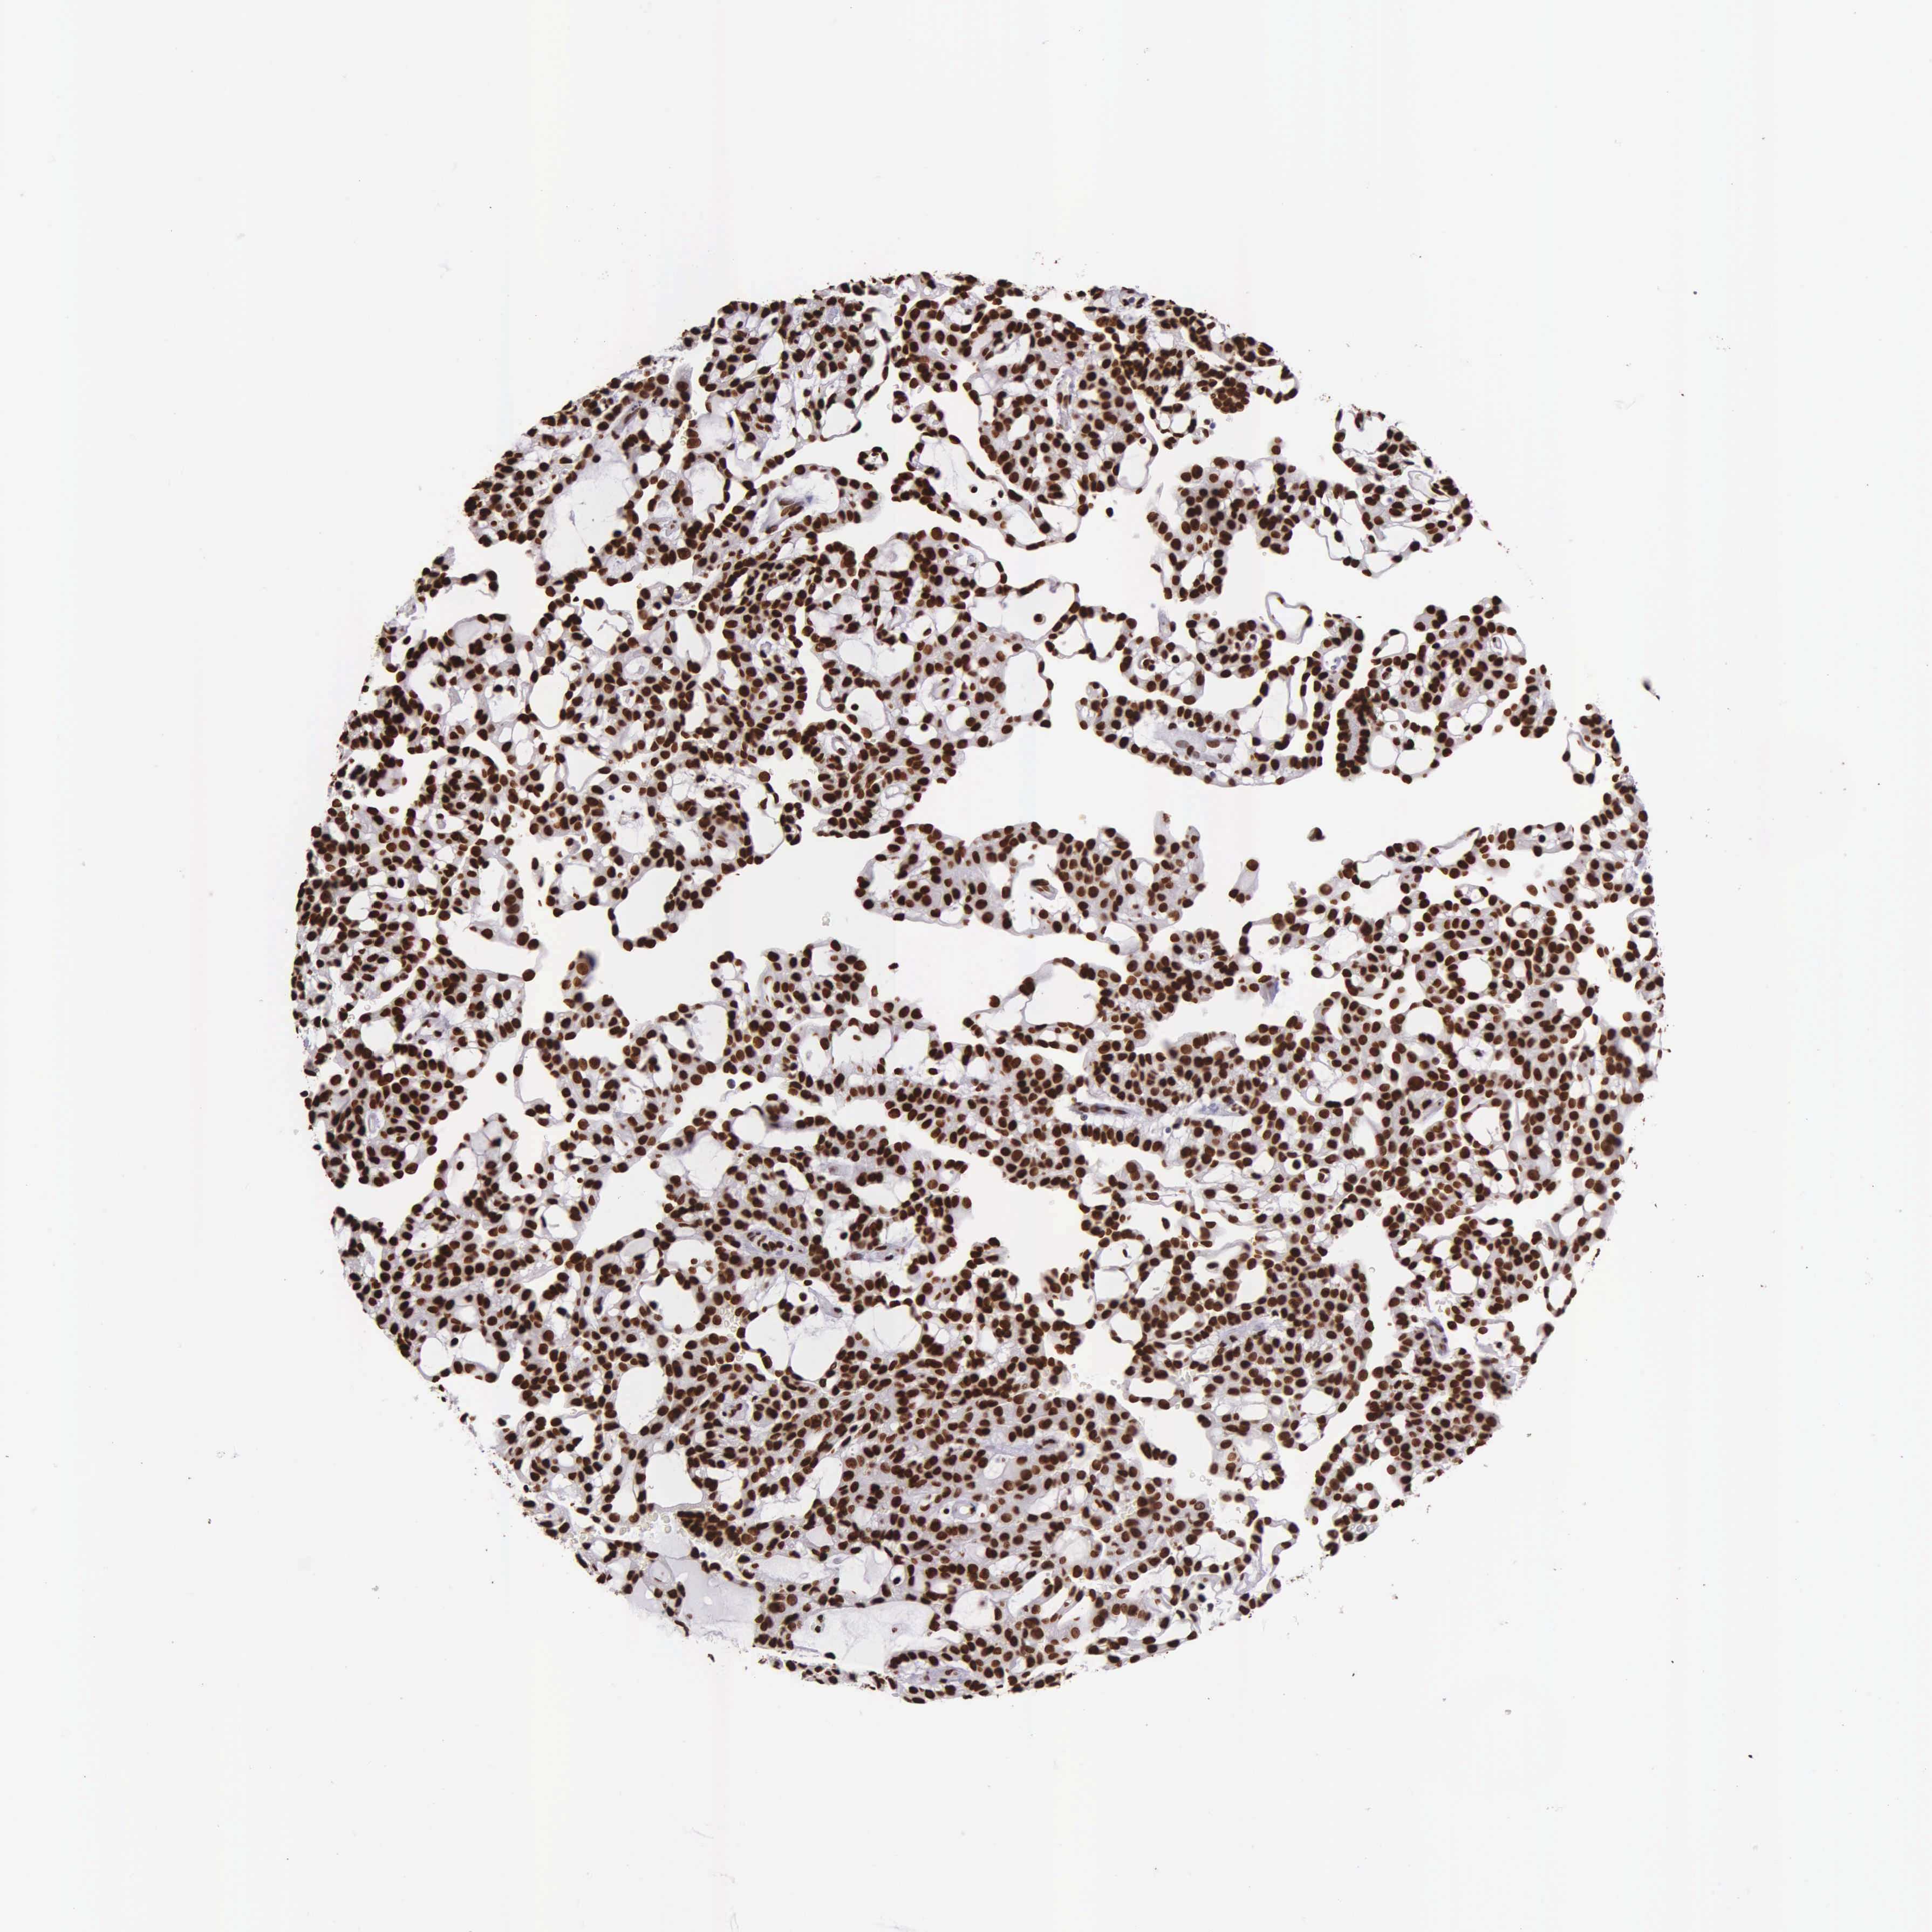

KIDNEY RENAL CLEAR CELL CARCINOMA (VALIDATION) - Interactive survival scatter ploti

The Survival Scatter plot shows the clinical status (i.e. dead or alive) for all individuals in the patient cohort, based on the same data that underlies the corresponding Kaplan-Meier plots. Patients that are alive at last time for follow-up are shown in blue and patients who have died during the study are shown in red.

The x-axis shows the expression levels (FPKM) of the investigated gene in the tumor tissue at the time of diagnosis. The y-axis shows the follow-up time after diagnosis (years). Both axes are complimented with kernel density curves demonstrating the data density over the axes. The top density plot shows the expression levels (FPKM) distribution among dead (red) and alive patients (blue). The right density plot shows the data density of the survived years of dead patients with high and low expression levels respectively, stratified using the cutoff indicated by the vertical dashed line through the Survival Scatter plot. This cutoff is automatically defined based on the FPKM cutoff that minimizes the p-score. The cutoff can be changed by dragging the vertical line or by entering a cutoff value in the square labeled "Current cut-off".

Under the Survival Scatter plot the p-score landscape (black curve; left axis) is shown together with dead median separation (red curve; right axis). Dead median separation is the difference in median mRNA expression between patients who have died with high and low expression, respectively. It is calculated as follows: median FPKM expression of dead patients with high expression - median FPKM expression of dead patients with low expression. This is intended to aid the user in visually exploring custom cutoffs and the associated p-scores and dead median separation.

Individual patient data is displayed and can be filtered by clicking on one or more of the category buttons on the top of the page. Categories describing expression level and patient information include: high, low, alive, dead, female, male and tumor stages. The scale of the x-axis can be toggled between linear and log-scale by clicking on the "x log" button. Mouse-over function shows TCGA ID, patient information and mRNA expression (FPKM) for each patient.

& Survival analysisi

Kaplan-Meier plots summarize results from analysis of correlation between mRNA expression level and patient survival. Patients were divided based on level of expression into one of the two groups "low" (under cut off) or "high" (over cut off). X-axis shows time for survival (years) and y-axis shows the probability of survival, where 1.0 corresponds to 100 percent.

H1-0 is not prognostic in Kidney Renal Clear Cell Carcinoma (validation)

Best expression cut offi

Based on the FPKM value of each gene, patients were classified into two groups and association between prognosis (survival) and gene expression (FPKM) was examined. The best expression cut-off refers the FPKM value that yields maximal difference with regard to survival between the two groups at the lowest log-rank P-value. Best expression cut-off was selected based on survival analysis .

When clicking on this number, the vertical dashed line indicating cut-off, the interactive survival plot, and the Kaplan-Meier curve will be adjusted to show results based on the best expression cut-off.

: 54.25

P scorei

Log-rank P value for Kaplan-Meier plot showing results from analysis of correlation between mRNA expression level and patient survival.

N/A

Average pTPM 75.7

Number of samples 100